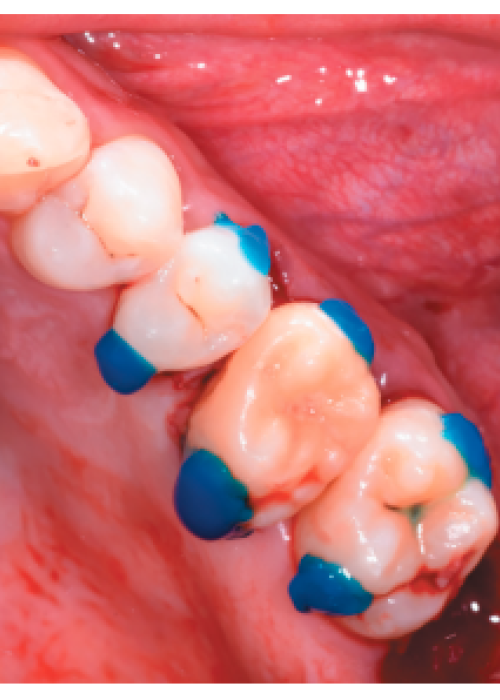

Reubicación quirúrgica de un segundo molar inferior. Presentación de un caso clínico y revisión de la literatura